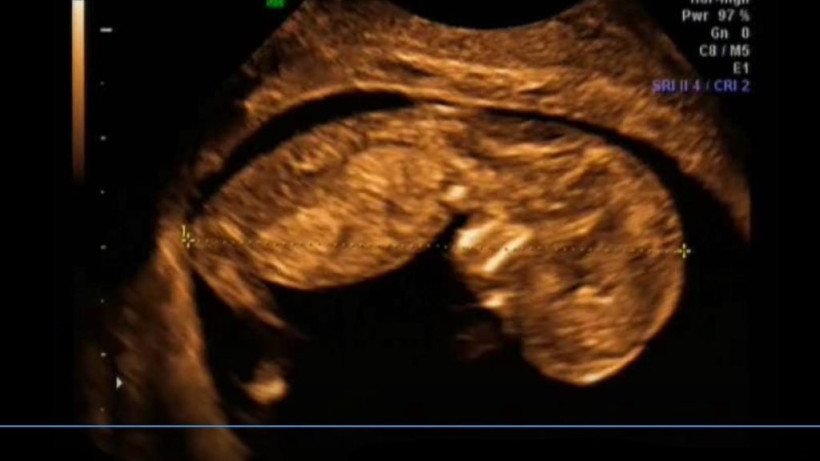

W 30. tygodniu życia Twojemu dziecko zaczyna być trochę ciasno. Fikanie koziołków nie jest już takie proste. Za to coraz aktywniejsza jest kora mózgowa. Twoje dziecko ma

15. tydzień życia Twojego dziecka to intensywny rozwój jego mózgu. Dziecko świetnie się bawi w Twoim brzuchu, doskonaląc ruch. A Ty lada moment poczujesz

7 i 8. tydzień życia dla to czas, kiedy wszystkie narządy Twojego dziecka już powstały i zaczynają pracować. Na kolejnych etapach rozwoju będą doskonalone, ale już teraz maleńki

10. tydzień życia dziecka to dalszy intensywny rozwój mózgu. W tym tygodniu powstanie trzy razy więcej połączeń nerwowo-mięśniowych niż w tygodniu ubiegłym. Twoje maleństwo

W 11. tygodniu życia wszystkie narządy dziecka są już ukształtowane. Ich doskonalenie jednak trochę jeszcze potrwa. Maleństwo ćwiczy nowe ruchy i staje się coraz sprawniejsze. Dziecko ma już 6,5

W 12. tygodniu życia Twoje dziecko ćwiczy wytrwale jak sportowiec. Ale potrafi też płakać! Maleństwo mierzy 7,5 cm długości i waży 14 g. Jest wielkości średniego jabłka. Co się dzieje

Odliczanie czas zacząć!